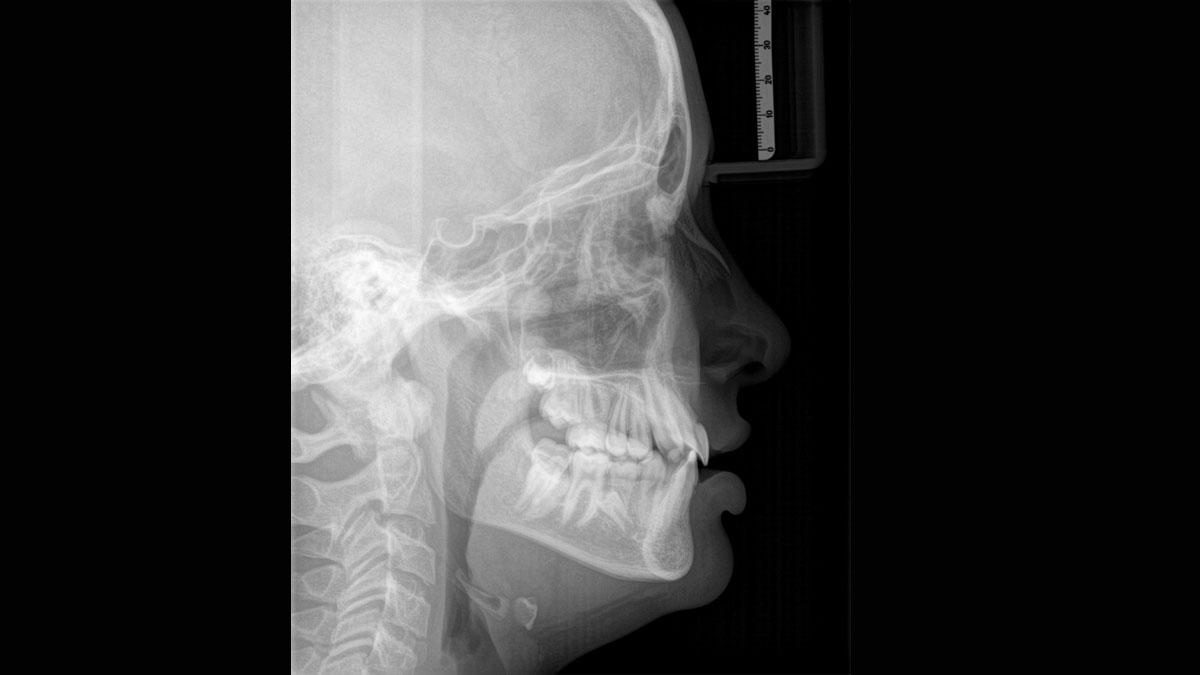

For exceptional panoramic images with high sharpness. You can choose an optional right or left cephalometric arm, which can be retrofitted at any time

When trying to capture a successful medical or dental X-ray there is an ongoing fundamental conflict. On the one hand, you want to do whatever it takes to acheive maximum image quality, on the other hand, the radiation dose should be as low as reasonably achievable for the patient. At Dentsply Sirona we are dedicated to offering products that ensure exceptional image quality while supporting safe and ethical practice. When developing our products, we observe the internationally valid ALARA principle (as low as reasonably achievable).

Thanks to the optimised low dose mode with a dedicated filter, the imaging of dense structures, such as bones, is possible at a greatly reduced dose. This makes Intelligent Low Dose an attractive and efficient option for many clinical situations. Whether in orthodontics or implantology - with Dentsply Sirona solutions you will find the optimum setting for every case.